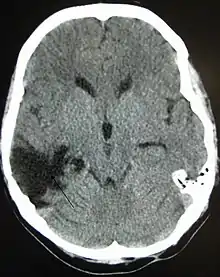

| A CT of the head years after a traumatic brain injury showing an empty space where the damage occurred, marked by the arrow |

There are several imaging techniques that can aid in diagnosing and assessing the extent of brain damage, such as computed tomography (CT) scan, magnetic resonance imaging (MRI), diffusion tensor imaging (DTI) magnetic resonance spectroscopy (MRS), positron emission tomography (PET), and single-photon emission tomography (SPECT). CT scans and MRI are the two techniques widely used and are most effective. CT scans can show brain bleeds, fractures of the skull, fluid build up in the brain that will lead to increased cranial pressure.[36]